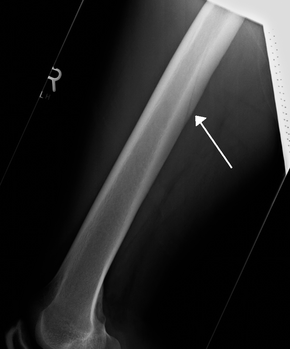

Nutrientvessel.png

A nutrient canal feeding the femur seen on X-ray